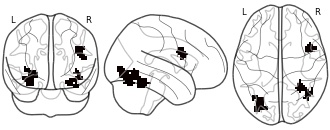

"name": "Multi_VBMgreater_fMRIenhanced",

"description": "Multi-modal analysis in BPD. Brain regions exhibiting greater gray matter and enhanced activation during emotion processing in BPD compared to healthy controls. Note: Results were thresholded at p<.0025. Note2: Results were updated (see Erratum for this publication).",